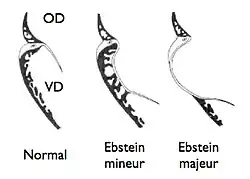

L'anomalie d'Ebstein est loin d'être univoque. Lorsque le défaut de clivage est minime, elle est souvent méconnue car sans aucun retentissement, le cœur fonctionnant dans des conditions quasi normales. À l'opposé, dans les formes majeures, la cavité ventriculaire droite est extrêmement réduite et incapable d'assurer la fonction qui lui est normalement dévolue. Entre ces deux extrêmes, tous les intermédiaires sont possibles.

Schématiquement, le pronostic néo-natal sera a priori bon dans les formes mineures et isolées. L'enfant peut même rester totalement asymptomatique et mener une vie tout à fait normale. Le seul risque serait celui de l'apparition de troubles du rythme cardiaque vis-à-vis desquels divers traitements habituellement sont efficaces. À l'opposé, on doit craindre le pire s'il s'agit d'une forme majeure ou s'il s'associe d'autres malformations, en particulier une communication inter-ventriculaire. Entre ces deux extrêmes, il est très difficile de poser un pronostic et les bonnes comme les mauvaises surprises ne sont pas rares. Cette incertitude fait qu'une interruption de grossesse peut être envisagée. Elle sera discutée au cas par cas.